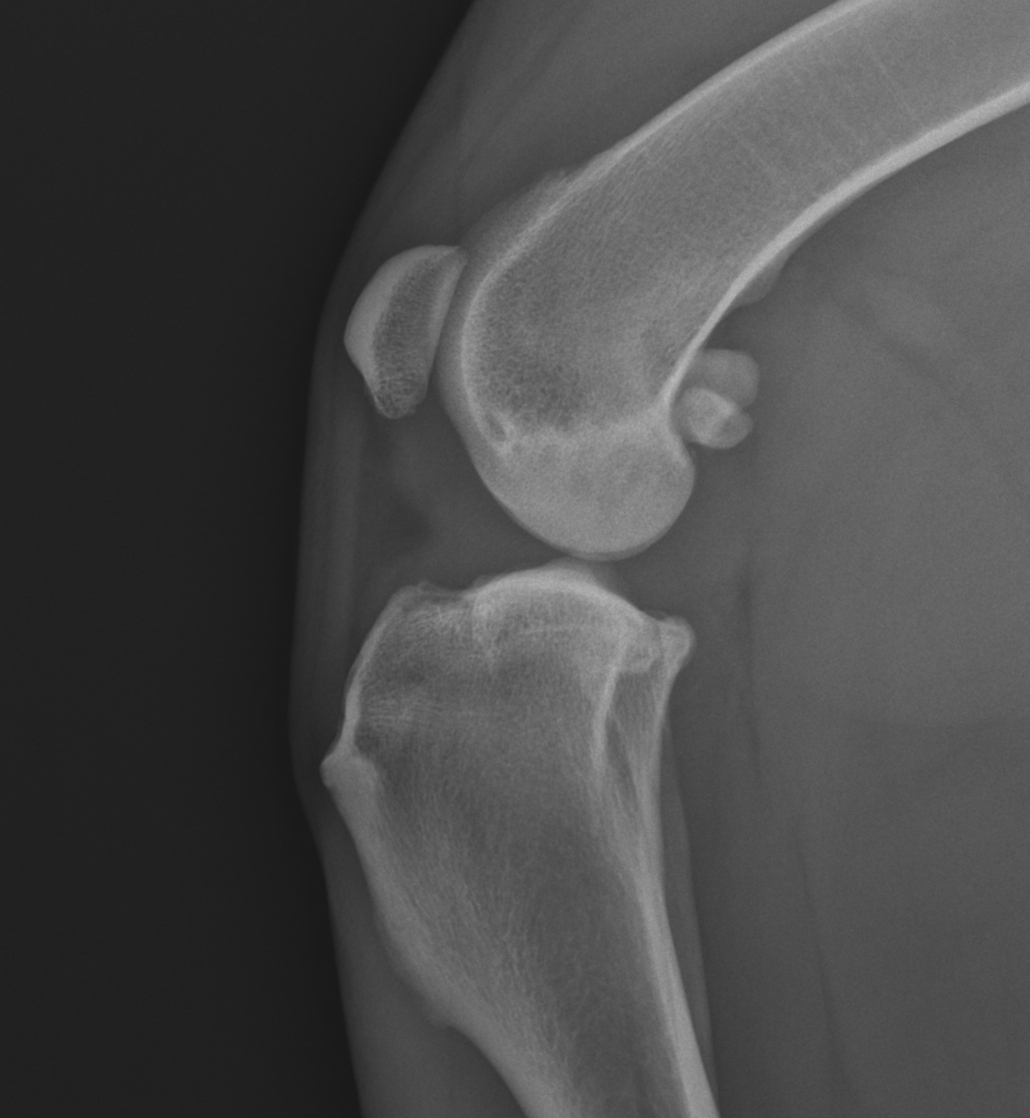

Veterinární ortopedie tak řeší poruchy pohybu zvířat, kulhání psů a koček, hledá příčiny tohoto kulhání a také tyto příčiny léčí. Veterinární ortoped má v dnešní době ohromné možnosti jak na poli léčby konzervativní (multimodální přístup – řízení pohybu, fyzioterapie, udržování ideální tělesné hmotnosti, nové léky proti bolesti, léčba magnetem, laserem, rázovou vlnou, kloubní doplňky výživy, nitrokloubní injekce), tak na poli léčby chirurgické (operace kloubů a kostí psů a koček, např. operace kolene u psů - operace při ruptuře zkříženého vazu u psů TPLO, dále operace luxace pately, operace kyčelních kloubů u dysplazie kyčelního kloubu psů a koček včetně totálních náhrad, operace dalších vrozených a vývojových ortopedických vad psů – operace dysplazie loketního kloubu psů, operace osteochondrózy a další.

Miniinvazivní vyšetření a ošetření kloubů zajišťuje u veterinárních klinik vybavených endoskopem artroskopie. Artroskopické vyšetření psů a koček je nejčastěji zaměřeno na diagnostiku vrozených vývojových onemocnění psů, jako jsou např. osteochondrózy psů a dysplazie loketního kloubu psů, a na nitrokloubní poranění, například ruptury šlach, ruptury vazů v koleni psů, poranění menisků apod. Odkaz na artroskopii